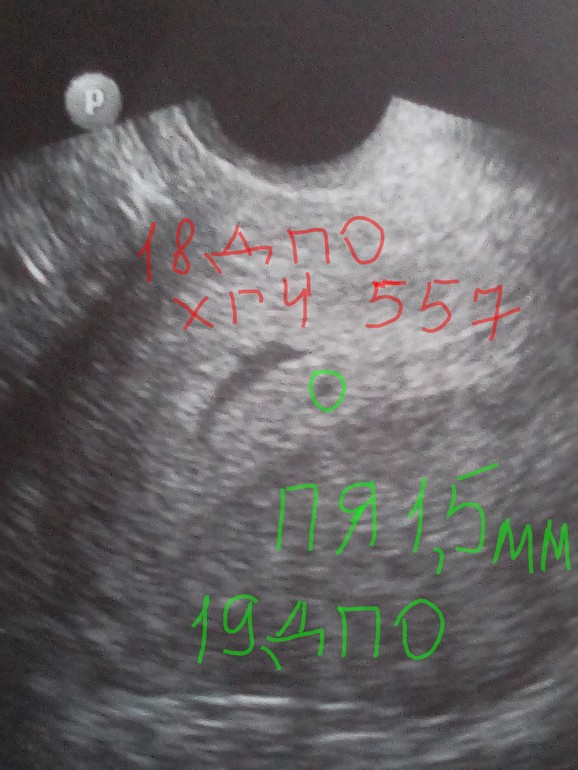

В 5+4( вагинальное):

В 4+4( вагинальное):